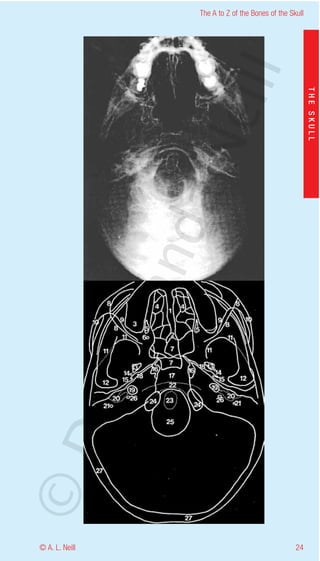

The A to Z of the Bones of the Skull

External Skull Inferior

eill

radiology submentovertical view

THE SKULL

1           Nasal septum (vomer and perpendicular plate of

the ethmoid)

2           Posterior border of vomer

aN

3           Maxillary sinus

4           Ethmoid sinus

5           Greater palatine foramen

6           Lesser palatine foramen

7           Sphenoid sinus

8           Posterior orbital margin - greater wing of the

nd

sphenoid

9           Posterior boundary of the maxillary sinus

10          Zygomatic arch

11          Lesser wing of the sphenoid

ma

12          Head of mandible condyloid process

13          Foramen ovalae

14          Foramen spinosum

15          Spine of the sphenoid

16          Foramen lacerum

17          Clivus - base of the occipital and sphenoid bones

rA

18          Eustachian tube - (pharyngotympanic tube)

19          Carotid canal

20          Jugular foramen

21          Stylomastoid foramen

22          Anterior arch of the atlas (C1)

©D

23          Odontoid process of axis (C2)

24          Occipital condyles

25          Foramen magnum

26          Canaliculus for tympanic nerve

27          Inner and outer tables of the skull - Diploe